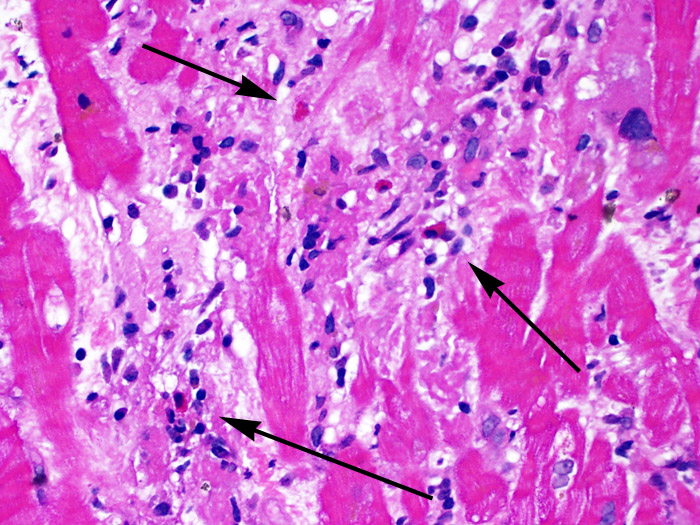

Межуточный миокардит: гистологические исследования

Раздел: Идеи и советы